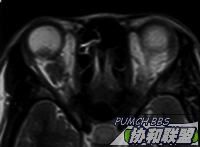

MRI  T1 & T2

图片点击可在新窗口打开查看